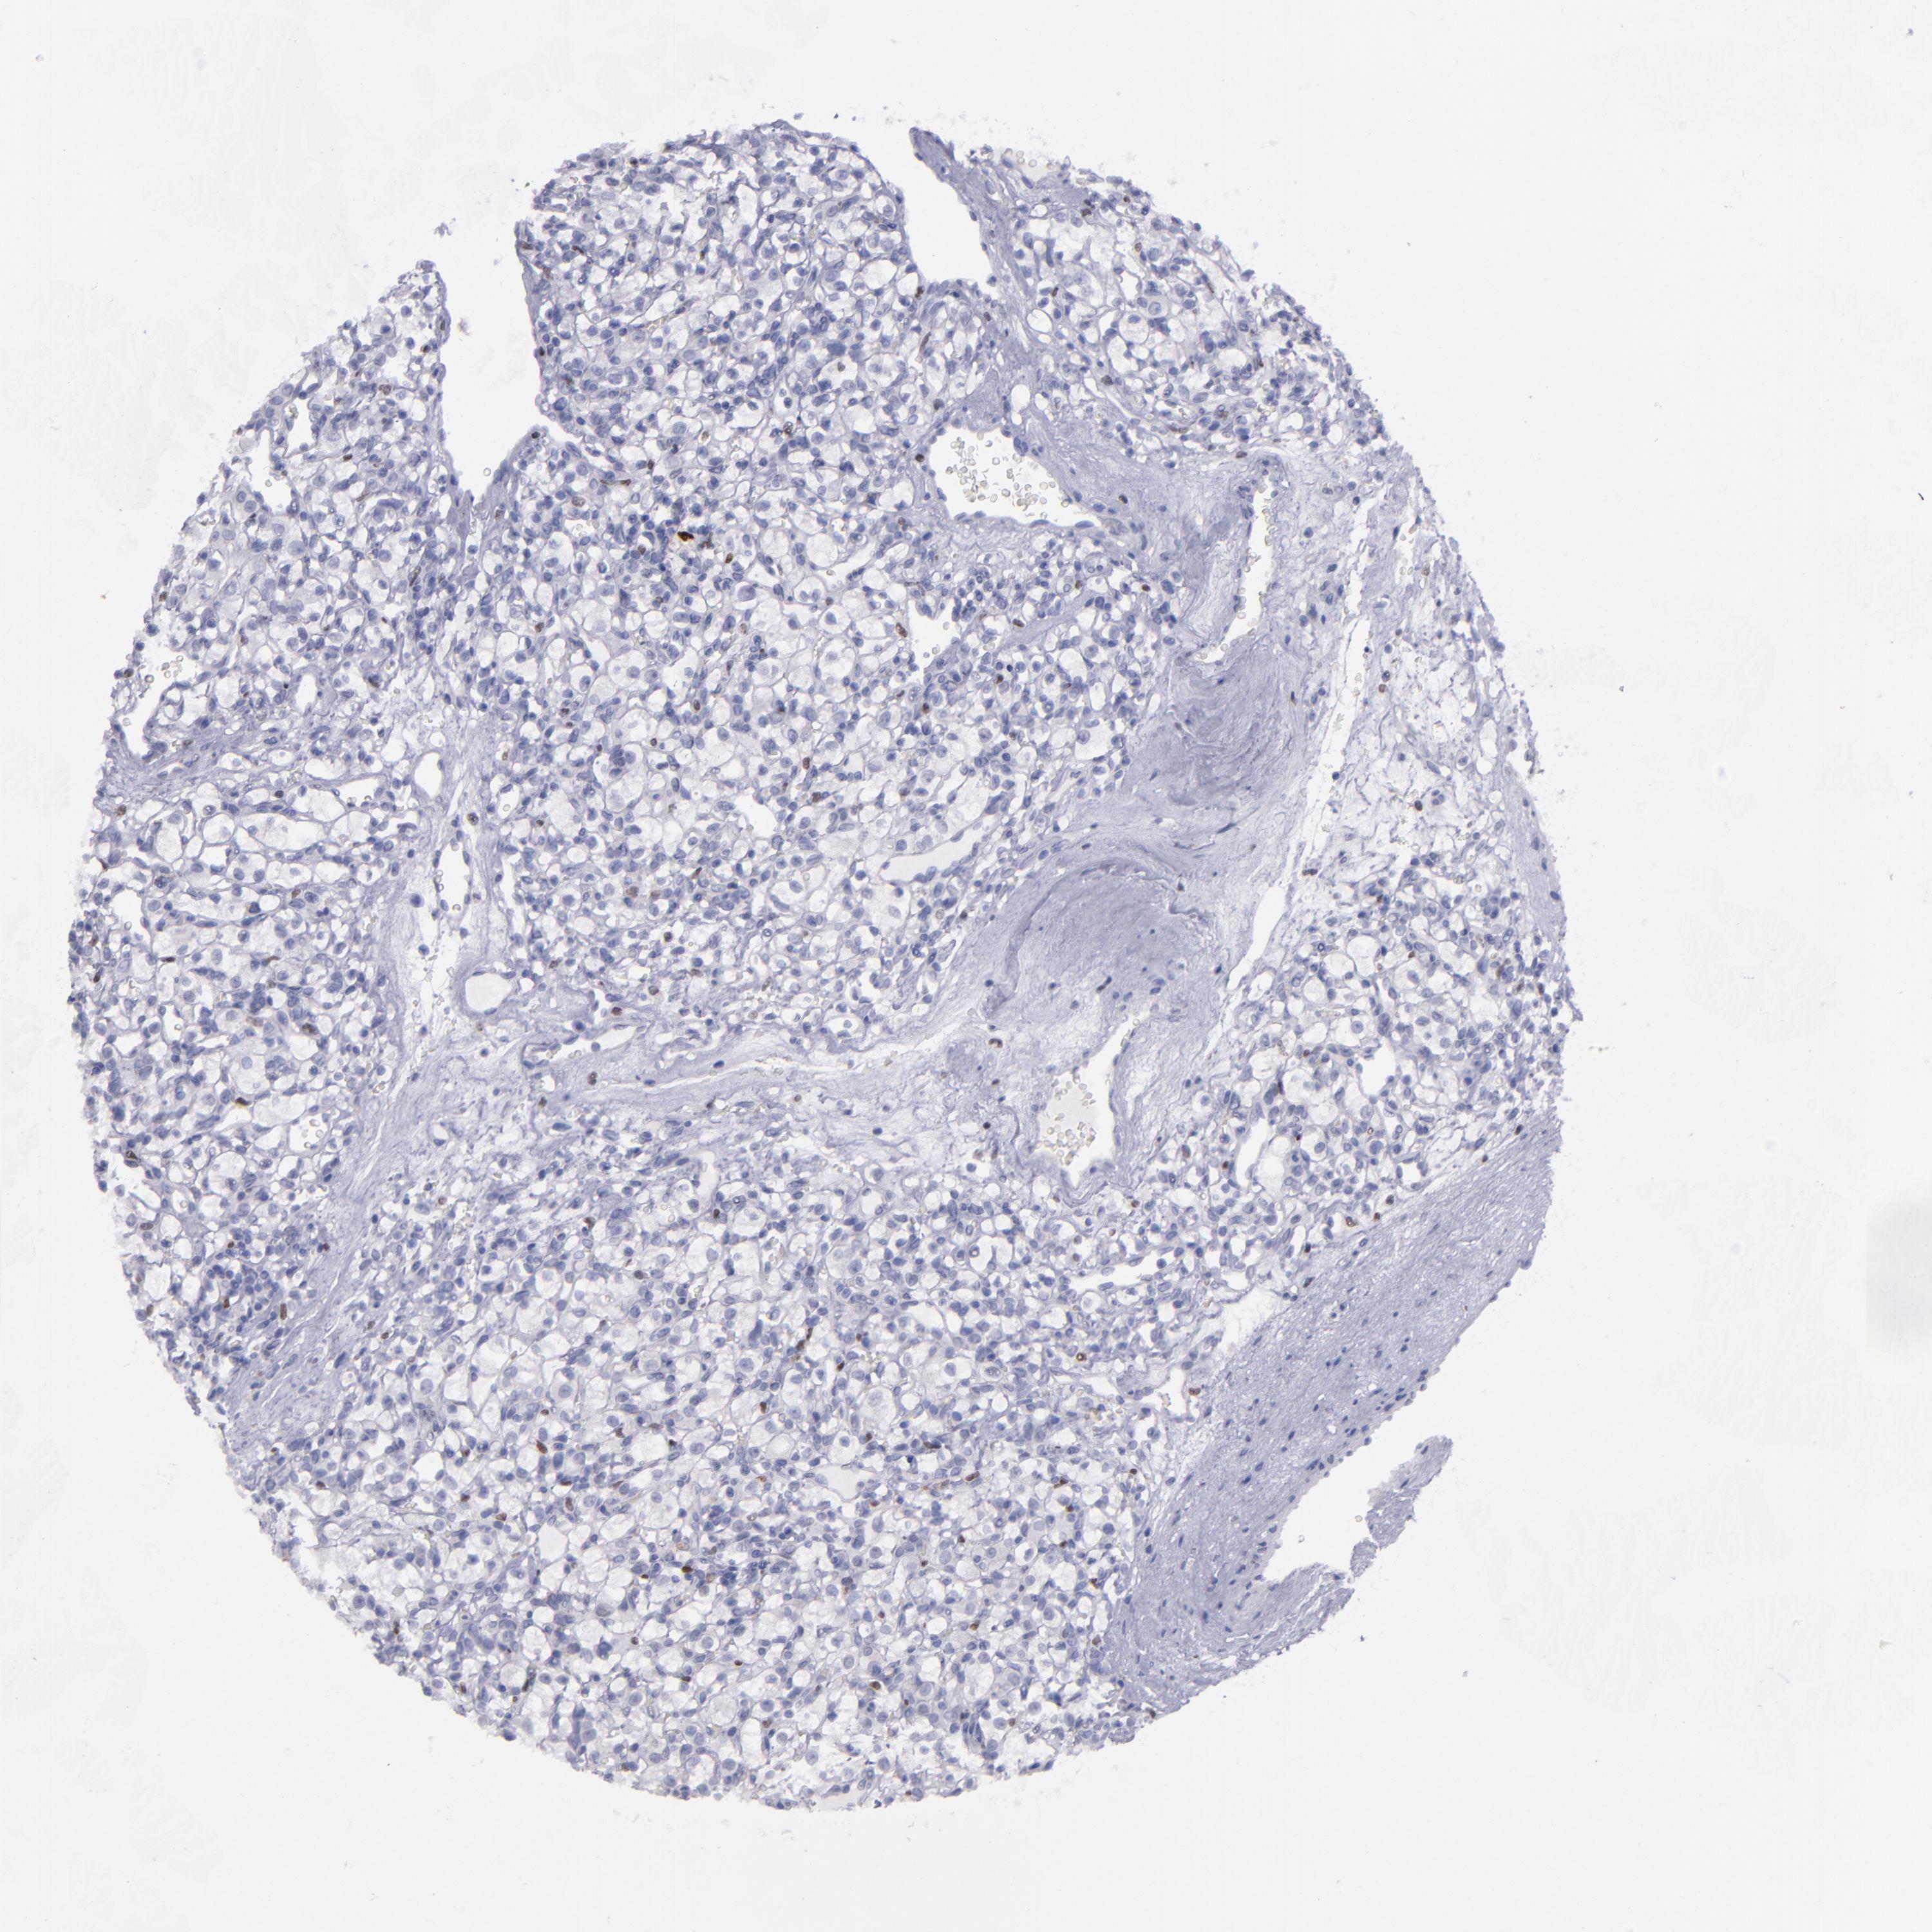

KIDNEY RENAL CLEAR CELL CARCINOMA (VALIDATION) - Interactive survival scatter ploti

The Survival Scatter plot shows the clinical status (i.e. dead or alive) for all individuals in the patient cohort, based on the same data that underlies the corresponding Kaplan-Meier plots. Patients that are alive at last time for follow-up are shown in blue and patients who have died during the study are shown in red.

The x-axis shows the expression levels (FPKM) of the investigated gene in the tumor tissue at the time of diagnosis. The y-axis shows the follow-up time after diagnosis (years). Both axes are complimented with kernel density curves demonstrating the data density over the axes. The top density plot shows the expression levels (FPKM) distribution among dead (red) and alive patients (blue). The right density plot shows the data density of the survived years of dead patients with high and low expression levels respectively, stratified using the cutoff indicated by the vertical dashed line through the Survival Scatter plot. This cutoff is automatically defined based on the FPKM cutoff that minimizes the p-score. The cutoff can be changed by dragging the vertical line or by entering a cutoff value in the square labeled "Current cut-off".

Under the Survival Scatter plot the p-score landscape (black curve; left axis) is shown together with dead median separation (red curve; right axis). Dead median separation is the difference in median mRNA expression between patients who have died with high and low expression, respectively. It is calculated as follows: median FPKM expression of dead patients with high expression - median FPKM expression of dead patients with low expression. This is intended to aid the user in visually exploring custom cutoffs and the associated p-scores and dead median separation.

Individual patient data is displayed and can be filtered by clicking on one or more of the category buttons on the top of the page. Categories describing expression level and patient information include: high, low, alive, dead, female, male and tumor stages. The scale of the x-axis can be toggled between linear and log-scale by clicking on the "x log" button. Mouse-over function shows TCGA ID, patient information and mRNA expression (FPKM) for each patient.

& Survival analysisi

Kaplan-Meier plots summarize results from analysis of correlation between mRNA expression level and patient survival. Patients were divided based on level of expression into one of the two groups "low" (under cut off) or "high" (over cut off). X-axis shows time for survival (years) and y-axis shows the probability of survival, where 1.0 corresponds to 100 percent.

IRF8 is not prognostic in Kidney Renal Clear Cell Carcinoma (validation)

Best expression cut offi

Based on the FPKM value of each gene, patients were classified into two groups and association between prognosis (survival) and gene expression (FPKM) was examined. The best expression cut-off refers the FPKM value that yields maximal difference with regard to survival between the two groups at the lowest log-rank P-value. Best expression cut-off was selected based on survival analysis .

When clicking on this number, the vertical dashed line indicating cut-off, the interactive survival plot, and the Kaplan-Meier curve will be adjusted to show results based on the best expression cut-off.

: 24.68

P scorei

Log-rank P value for Kaplan-Meier plot showing results from analysis of correlation between mRNA expression level and patient survival.

N/A

TCGA RNA samplesi

RNA-seq data is reported as average FPKM (number Fragments Per Kilobase of exon per Million reads), generated by the The Cancer Genome Atlas (TCGA) .

Normal distribution across the dataset is visualized with box plots, shown as median and 25th and 75th percentiles. Points are displayed as outliers if they are above or below 1.5 times the interquartile range. FPKM values of the individual samples are presented next to the box plot.

Average pTPM 28.5

Number of samples 100